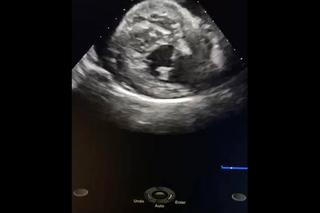

Od razu po wykonanych badaniach okazało się, że stan Czarnego jest na prawdę bardzo poważny! W jego worku osierdziowym nagromadziła się duża ilość płynu, która uniemożliwiała prawidłowy rozkurcz mięśnia sercowego. Badanie EKG wykazało migotanie przedsionków. Zaczęła się walka o jego życie.

-Od razu wykonano zabieg pericardiocentezy polegający na nakłuciu worka osierdziowego specjalną igłą w celu upuszczenia zalegającego płynu, który od razu został wysłany do laboratorium w celu zbadania. Kilka dni toczyła się walka o ustabilizowanie rytmu serca Czarnego. Wynik badania sugerował, iż nagromadzenie się płynu było spowodowane stanem zapalnym osierdzia. Wdrożono odpowiednią antybiotykoterapię. Codzienne kontrole, wspaniała współpraca z właścicielem oraz przede wszystkim zespołowa współpraca pomiędzy internistą, a kardiologiem sprawiły, ze Czarny w dniu dzisiejszym zakończył oficjalnie walkę o swoje życie!- podsumowali pracownicy Ady. Psiak wrócił do domu ze swoim właścicielem całkowicie zdrowy, pełen energii i znów gotów do zabaw.